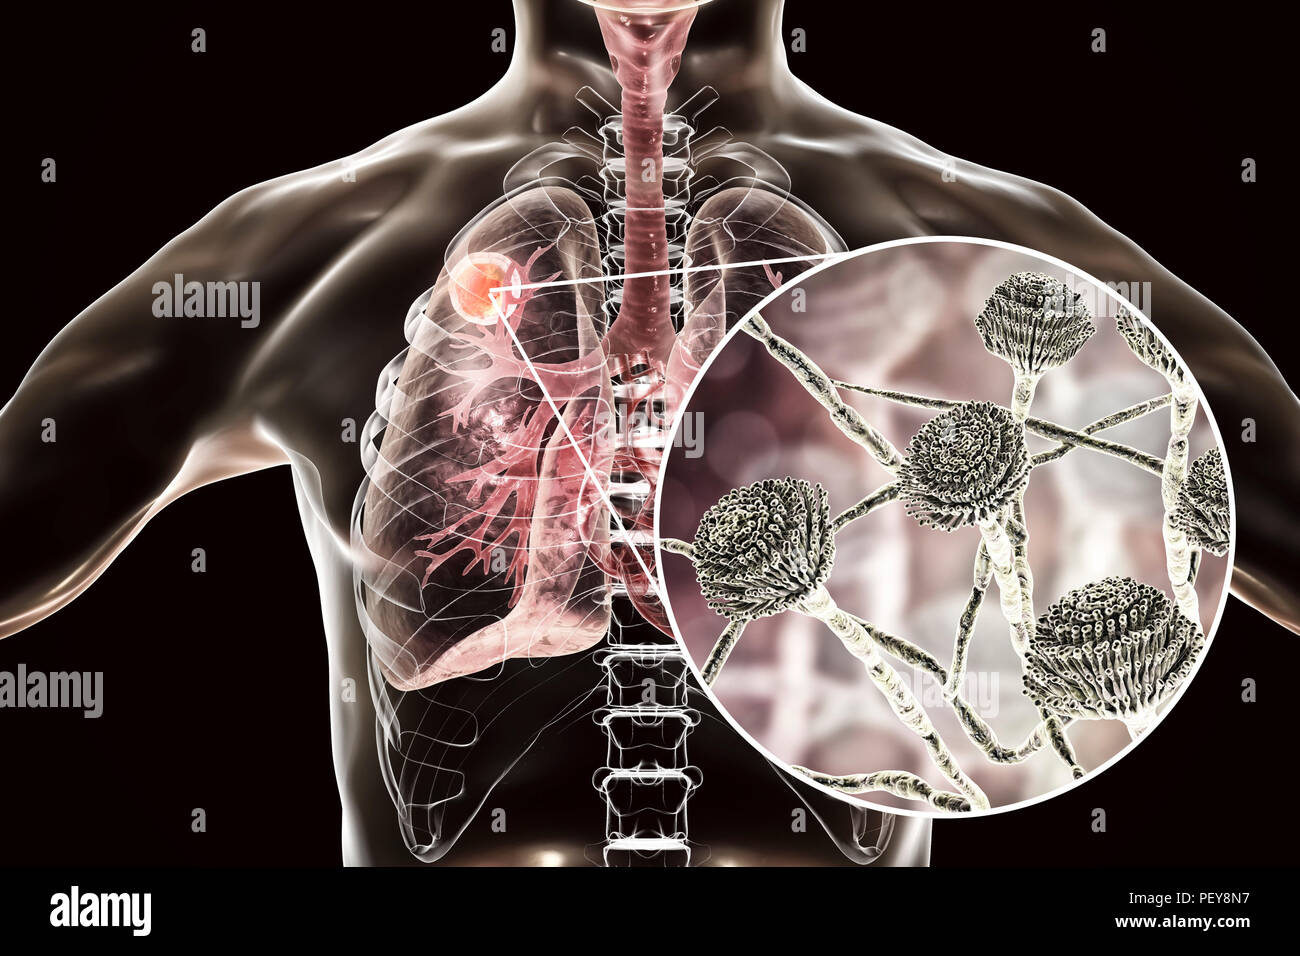

Aspergilloma del polmone e una vista ravvicinata di funghi Aspergillus, illustrazione del

Eziologia dell'edema polmonare le cause dell'accumulo di liquido negli alveoli polmonari